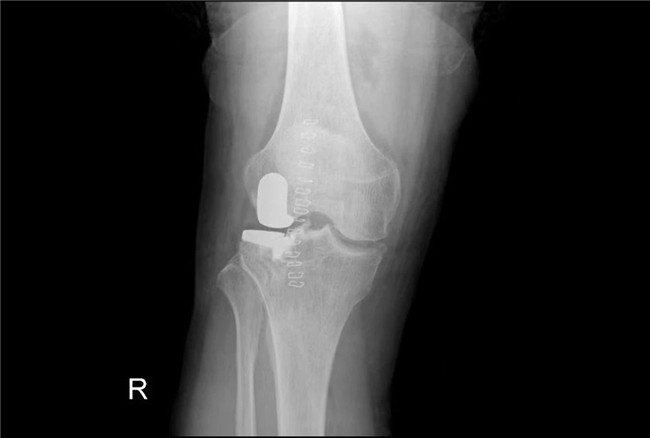

▲術(shù)后假體位置良好,外側(cè)間隙恢復(fù)▲

一個(gè)單髁置換手術(shù)要想達(dá)到理想的手術(shù)治療效果并不簡(jiǎn)單,這與假體的大小、方向和松緊度密切相關(guān),其中任何一點(diǎn)出現(xiàn)差池,結(jié)果都會(huì)差強(qiáng)人意。為此,羅主任團(tuán)隊(duì)在術(shù)前和術(shù)中進(jìn)行了精確的設(shè)計(jì)和測(cè)量,制定周密手術(shù)方案,順利為病人實(shí)施手術(shù),幫助膝關(guān)節(jié)“補(bǔ)牙”。